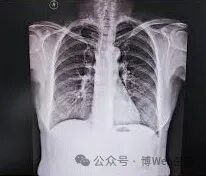

X光片可以看到肺部片状浸润或间质性改变,需排除其他类型肺炎。